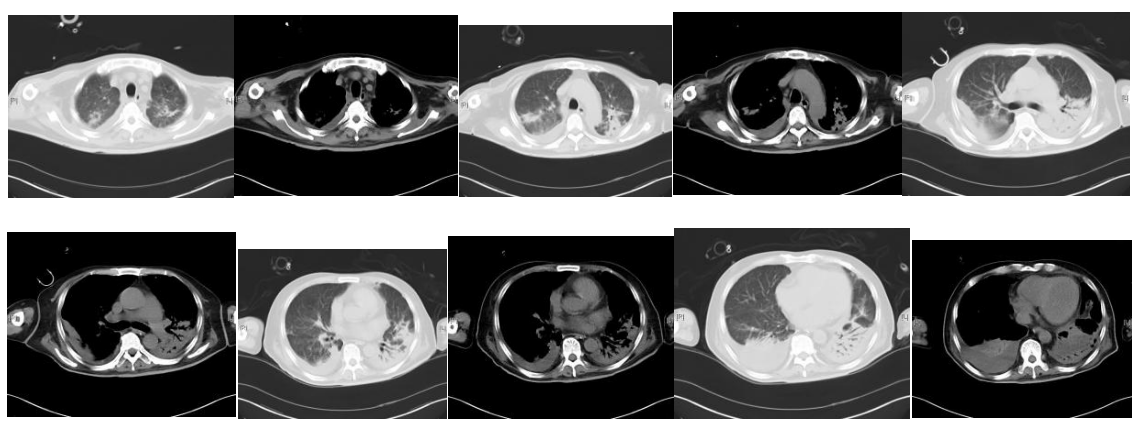

疗效评价:患者未再发热。神智清楚、言语欠清楚,左侧肢体肌力进一步下降。呼吸衰竭相对稳定,氧合指数维持在200 mmHg以上。血象无明显恢复,仍是持续粒细胞缺乏、中度贫血、血小板减少(波动在2万~5万)。7月28日复查胸部及头颅CT:双肺病变加重并出现双侧大量胸腔积液;右侧侧脑室、丘脑旁低密度,双侧上颌窦炎,真菌感染可能。再次行气管镜并送检灌洗液mNGs。并双侧胸腔置管引流,提示渗出性胸腔积液,留取胸水送检mNGS。灌洗液及胸水mNGs仍提示嗜肺军团菌。患者出现的肢体功能障碍,明确为脑梗塞导致,因患者持续存在血小板低下及凝血功能异常,未予抗凝及抗血小板治疗。

图10. 胸部CT(2023-07-28)

图11. 头颅CT(2023-07-28)